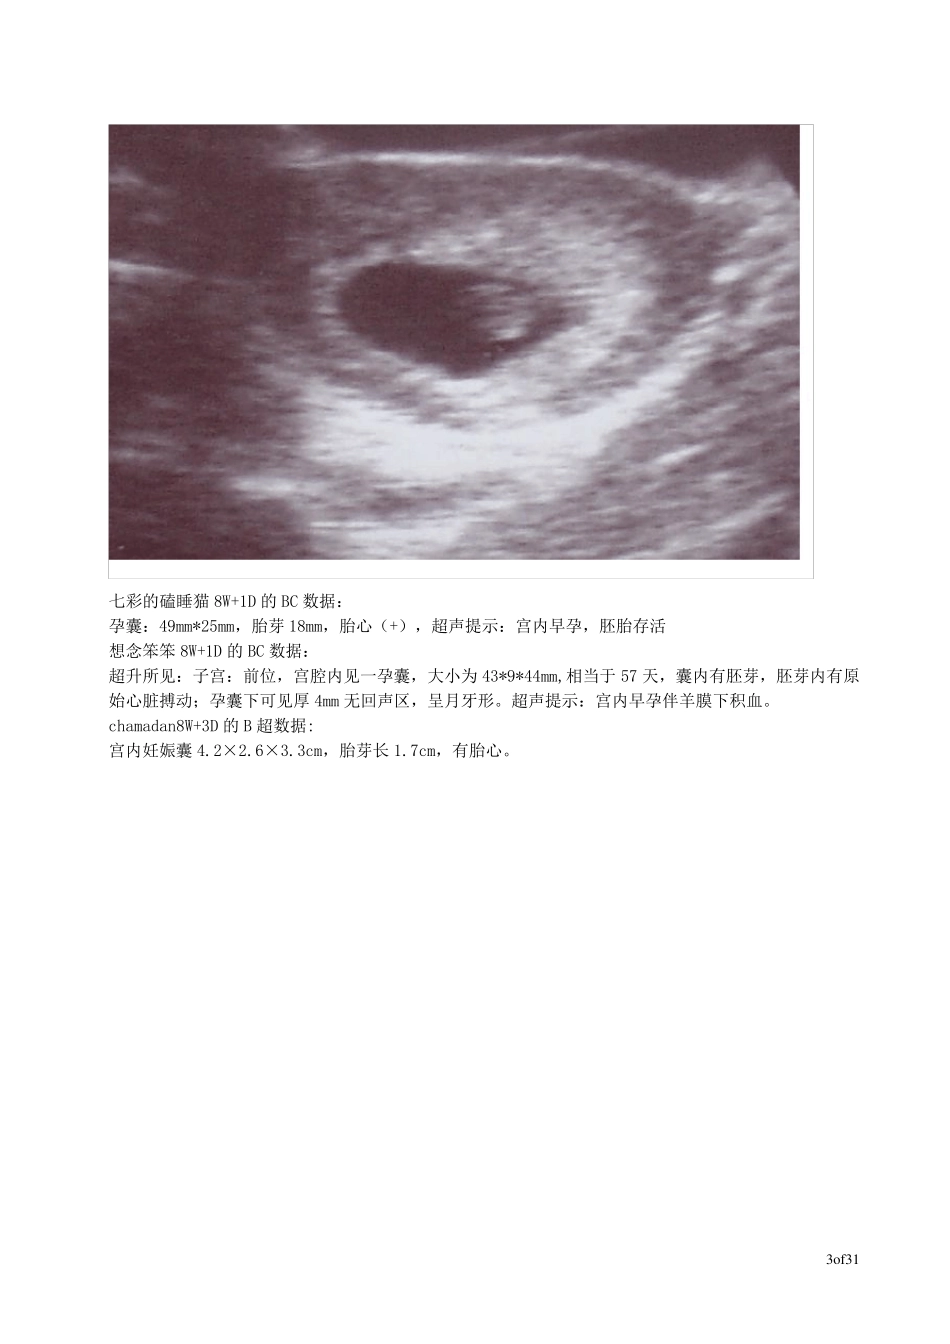

1o f31 孕早期的B 超数据集: xizi77 5W+5D 的BC 数据: 胚囊0.8X0.7X0.5CM 七彩的磕睡猫5W+6D 的BC 数据: 孕囊:25mm*11mm,未见胎心及胎芽。超声提示:宫内早孕 韵儿 5W+6D 的BC 数据: 子宫前端可见0.85CM*0.85CM 光影, 未见卵黄囊,胎牙及胎心 岚儿 6W 的BC 数据: 胚囊24*10*19mm,可见胚芽 E 宝宝 6W+1D 的B 超数据: 孕五周的样子,胎囊1.3cm smart6W+1D 的BC 数据: 胎囊2.7*1.1,可见卵黄囊,可见胚芽,胚芽0.4CM,似有胎心搏动 想要个宝贝 6W+3D 的B 超数据: 见孕囊,未见胎心及胎芽。超声提示:宫内早孕 xinpin6W+4D 天 B 超数据: 孕囊:20*17*17, 胎心:有,胎芽:有 相当于孕43 天 生个宝宝玩 7 周 BC 数据: 子宫中,后,大小:长 51 宽 60 厚 45 GS 位于宫腔右侧底部近宫角(没有大小) 蝴蝶梦 7W+1D 的BC 数据: 2o f31 54 照的b 超,但因为排卵迟了四天,该是50 天,结果:子宫:64x64x50、胚囊:23x17x16、见少许胚芽、两侧附件未见(膀胱尿未充盈)。提示:宫内早孕。准备三个月再照,现在70 天了 柠檬树7W+1D 的B 超图: smart7W+1D 的BC 数据: 胎囊2.9*1.9,胎芽1.2cm,有胎心搏动 jiong_xi7W+3D 的B 超数据: 胎囊4.2X2.2CM,胎芽1.3CM,可见胎心搏动。 笑笑妮7W+4D 的B 超数据: 子宫前位增大,宫内见孕囊,大小35*24 mm,内见胚芽,长10mm,可见原始心管搏动,可见卵黄囊,双侧附件区未见明显异常。 haruka7W+4D 的B 超数据: 增大的子宫腔内可探及一27×30×16mm的妊娠囊,妊娠囊的形态,位置正常,囊内可见胚芽,可见胎心博动,可见卵黄囊回声。 期待天使 7W+5D 的B超数据: 子宫附件:子宫位置 前位,宫体增大 宫内见一孕襄,大小约 34*25*23mm,内可见胚芽及心管博动,双附件无殊。 超声提示:宫内早孕 baier7周多的B 超数据: 子宫前屈位,切面内径74*54*65,形态增大,回声均匀。宫内见一孕囊,囊内见胚芽,见心管博动。双附件未见异常,盆腔未见积液。超声提示,宫内孕,胚胎存活。 这是我 8 周的B 超数据: 子宫增大,宫内见3.8*2.3CM 妊娠囊,囊内可见胎芽,及原始心管博动。 3o f31 七彩的磕睡猫8W+1D 的BC 数据: 孕囊:49mm*25mm,胎芽18mm,胎心(+),超声提示:宫内早孕,胚胎存活 想念笨笨8W+1D 的BC 数据: 超升所见:子宫:前位,宫腔内见一孕囊,大小为43...